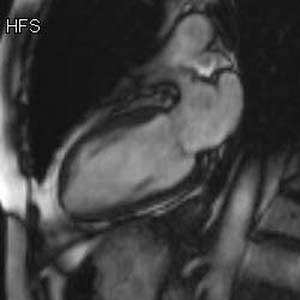

The coronary arteries can be indirectly evaluated by assessing myocardial function in the territory perfused by a given artery.

Mouse over each image to display the typical perfusion territories.

Short axis |